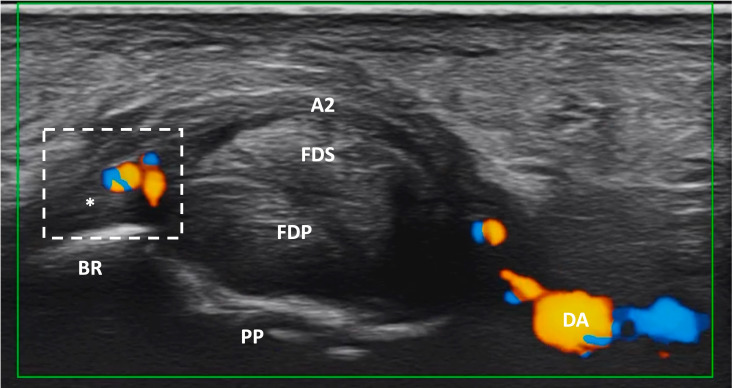

High-frequency ultrasound can detect inflammatory changes of the finger pulleys anatomical entheses in early psoriatic arthritis.

高频超声可检测早期银屑病关节炎指轮解剖腔炎性改变。